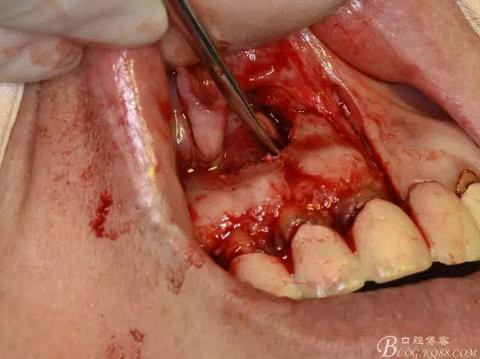

圖9.去除唇側薄的骨壁,暴露出囊壁

圖10.剝離囊壁